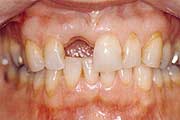

Wann machen Implantate Sinn?

Einzelzahnersatz

Gesunde Nachbarzähne müssen nicht beschliffen werden. Eine

unauffällige und natürliche Lösung. Anspruchsvoll in

der Ästhetik und langfristig im Nutzen.